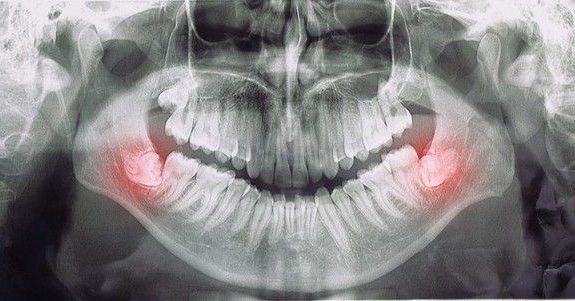

“Sem comentários para agradecer e elogiar o tanto que merecem! Sou muito grata a Deus por ter “caído” na busca desse consultório! Outrora, eu havia tentado tirar meu siso por umas 5x, a dentista não conseguia, a anestesia nao pegava, foi uma tortura, tomei antibiótico antes, depois, durante e nada, foram uns 7 dias pra mais! Deixei pra lá e depois de um tempo, eu procurei tratamento, bem traumatizada, confesso, iria fazer no particular e ao ver a boa fama do dr, imaginei que só conseguiria pagar vendendo um órgão hahahhaah não fui cobrada na avaliação, a Rita de uma elegância ímpar, e o dr? O que falar dele? Sem comentários pra fineza, simpatia, empatia, transparência e propriedade no que fala e mostrando que nasceu pra fazer o que faz. Com muito medo, voltei pra tirar esse dente que me tirava o juízo hahaha tomei remédio antes e estou tomando durante, foi tudo um SUCESSO, sem dor com uma anestesia, em 1 dia, e em menos de 1 hora (eram 2), e por um valor que até agora estou muito feliz pq coube e foi mais baixo do que com dentistas e não com bucomaxilo. Agradeço demais a todos da clínica, a Rita, ao dr Cesar, ao dr que o auxiliou, a Andreza- sem palavras. Dr. obrigada por tudo e por se deixar cumprir seu propósito na terra e ajudar tantas vidas!”

Dr. César é um excelente profissional, antes de conhecer a clínica estava com muito medo de extrair os meus sisos, mas ele me passou confiança e tirei 3 sisos, a cirurgia e o pós operatório foi muito tranquilo. Recomendo muito.

Dr César Donadio é um profissional de primeiro mundo. Extraiu 3 dentes meus sem nenhuma dor. Indico e recomendo por onde eu passar. Merece aplausos pelo seu profissionalismo!!